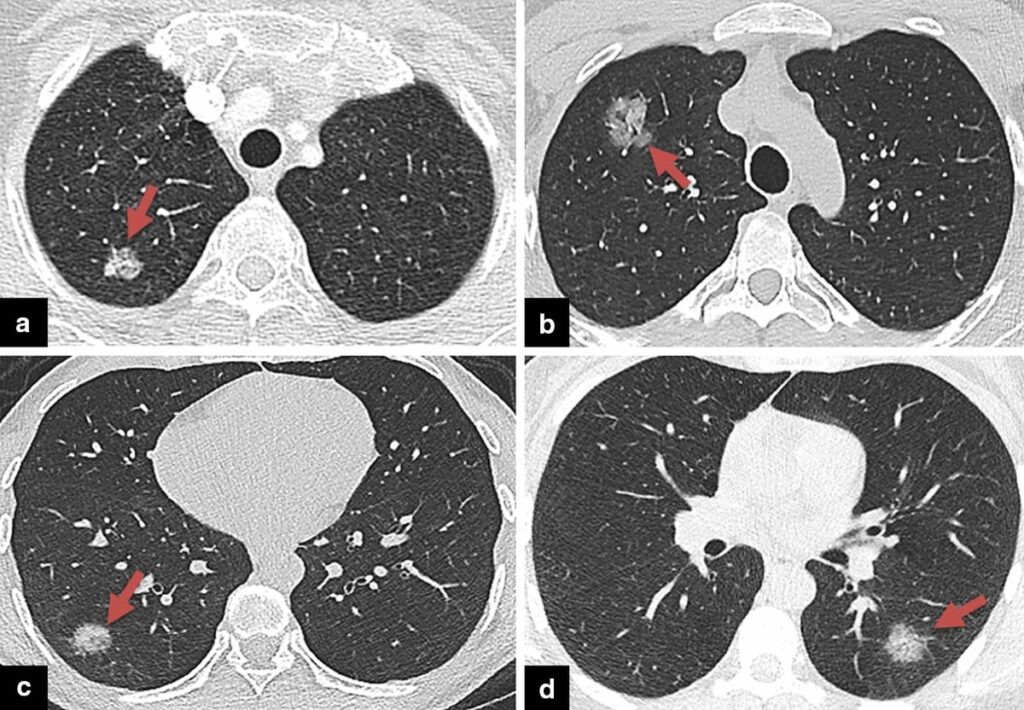

- Konsolidering: Dette er det mest almindelige fund. Konsolidering betyder, at lungevævets små luftsække (alveoler) er fyldt med væske, pus og celler i stedet for luft. På en CT-scanning ses dette som tætte, hvide områder. Ved Legionella er disse konsolideringer ofte pletvise (patchy) og kan involvere flere lapper af lungen (multilobære), ofte startende i de nedre dele af lungerne.

- Matglasinfiltrater (Ground-Glass Opacities): Dette er et andet hyppigt fund. Matglasinfiltrater beskriver områder i lungen, der ser tågede eller slørede ud på scanningen, som at kigge gennem mat glas. Det indikerer en delvis fyldning af luftsækkene eller en fortykkelse af vævet omkring dem. Disse områder findes ofte omkring de mere tætte konsolideringer og kan være et tegn på, at infektionen spreder sig.

- Hurtig progression: Et karakteristisk træk ved Legionella er, at forandringerne i lungerne kan udvikle sig meget hurtigt. En patient kan gå fra at have mindre pletter til udbredt konsolidering i begge lunger på bare 2-4 dage. Opfølgende CT-scanninger kan visualisere denne progression og hjælpe med at vurdere, om behandlingen virker.